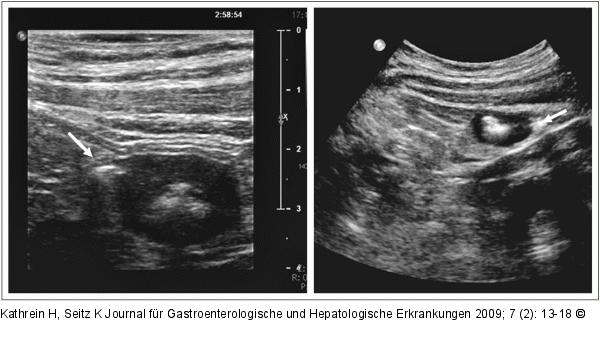

Abbildung 1: Blande Divertikel Blande Divertikel: Querschnitt durch das Colon descendens. Man erkennt die echoarme Wandverdickung und seitlich adhärent ein echogenes Divertikel (Pfeil) mit Schallschatten. |

Blande Divertikel: Querschnitt durch das Colon descendens. Man erkennt die echoarme Wandverdickung und seitlich adhärent ein echogenes Divertikel (Pfeil) mit Schallschatten. |